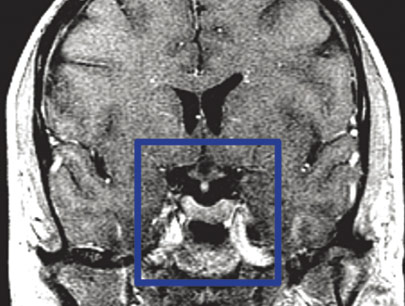

AVM (Arterivenous Malformation)

Kelainan pembuluh darah otak non-stroke

SEBELUM

SESUDAH